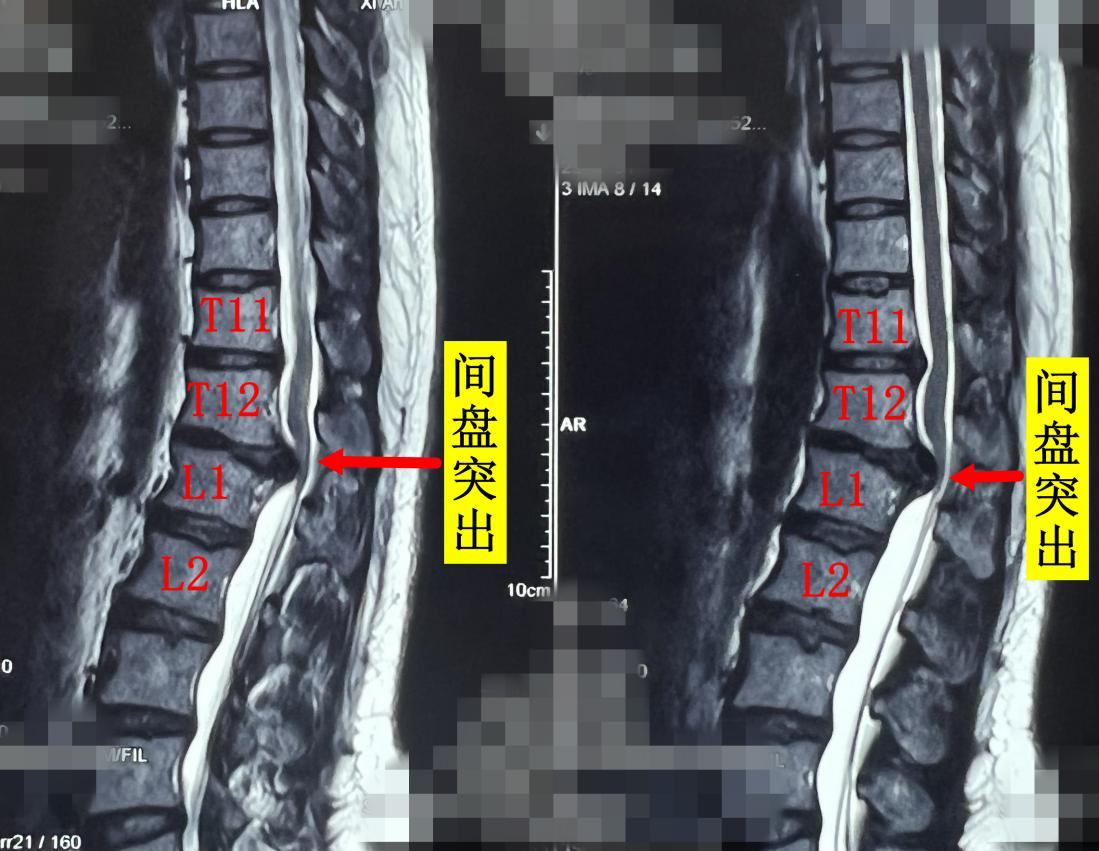

杨俊松副主任医师接诊后结合患者病史、体征和影像学资料指出,患者胸12 腰1椎间盘突出症诊断明确,双侧脊髓神经严重受压,椎间盘严重钙化。

MRI显示:间盘突出&脊髓神经严重受压